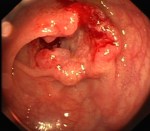

[Left] Polyps in the colon. [Right] Cancer in the Colon/Rectum area.

Cleo had her endoscopy and colonoscopy done after the Chinese New Year of 2017. The doctor didn’t find ulcers or parasites. They found some nodules in parts of her colon and rectum. A such, they did a biopsy on some of those abnormal tissue and sent those to the labs for examination.

Imagine the shock Cleo had when her doctor called her and her husband in for an urgent discussion. He revealed that the tissue were an aggressive malignant tumour that has penetrated the sub-mucosa and affected a large section of her colon and rectum. He recommended immediate surgery before it spread further and penetrate deeper!

Cleo then did a CT scan and went for a surgery to remove 60cm of her lower colon and upper rectum. The doctor has also recommended chemo-therapy if the CT scan shows the cancer has spread to the lymph nodes or other organs. Fortunately the cancer has not spread and she was spared a really painful treatment with unpleasant side-effects.